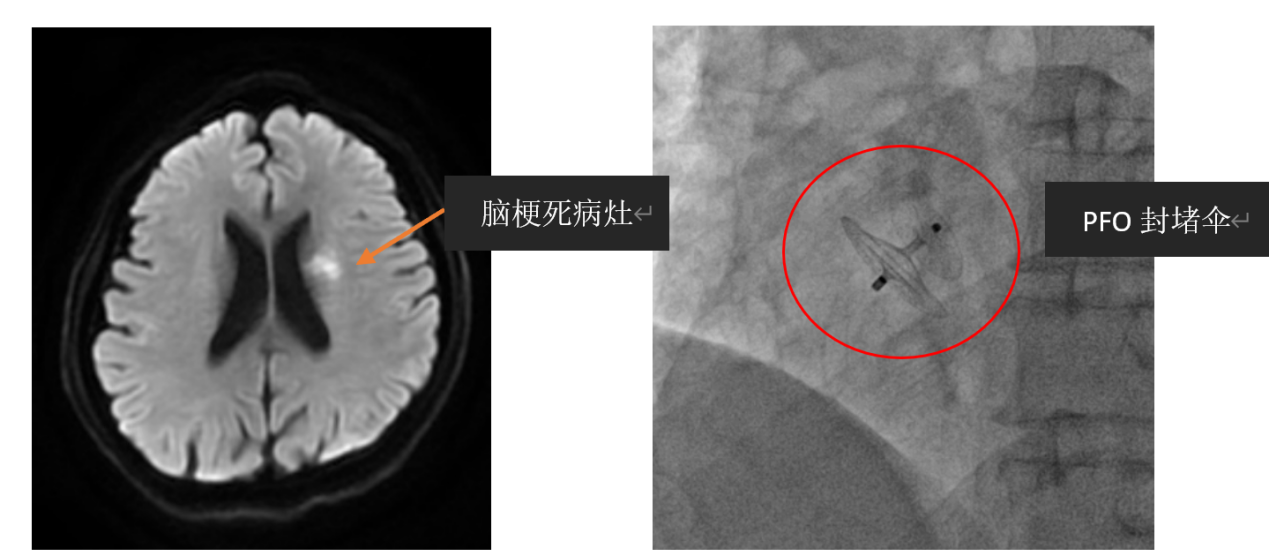

为查明病因,张小峰继续为患者完善经颅多普勒超声(TCD)发泡试验与右心超声造影检查,发现有多发栓子信号,结果提示患者卵圆孔未闭(PFO)。原来,患者的脑梗竟是来源于心脏卵圆孔未闭导致的反常性栓塞。

确诊后,患者转诊至我院心血管中心,心血管内科介入学组副主任医师薛亚军,带领主治医师张鸥、韩治伟,顺利通过微创为患者完成经血管卵圆孔封堵术,减少了患者脑梗复发的风险。

隐源性卒中患者应常规开展卵圆孔未闭的筛查,对卵圆孔未闭引起的栓塞性缺血性脑卒中患者,为预防脑卒中复发,除应用抗血栓药物治疗外,一个重要方案是采用微创,在超声或X线指导下用装置封堵卵圆孔,具有时间短,创伤小的特点,术后1-2天即可恢复正常工作和生活,帮助减少复发性脑卒中风险,比单纯抗血小板等药物治疗更有效。